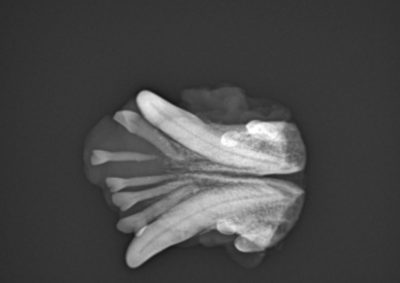

腫瘍外科 注意 ボタンをクリックした先に、治療中および手術中の画像が説明で使用されている場合がございます。 そのような画像に弱い方は閲覧なさらないようお願いいたします。 腫瘍外科 フレンチブルドッグ胃腺癌 胃部分切除 軟部組織外科腫瘍外科救急・集… 肝臓腫瘤破裂による腹腔内出血 腫瘍外科腫瘍内科 猫の直腸切除吻合 直腸リンパ腫 腫瘍外科 犬の肺腺癌の1例 腫瘍外科放射線治療 犬の軟部組織肉腫に対する腫瘍辺縁切除及び術後放射線療法 腫瘍外科 犬の肝細胞癌 軟部組織外科腫瘍外科 ジャックラッセルテリアの胃腫瘍 腫瘍外科 吻側下顎骨切除術〜メラノーマ〜 腫瘍外科 猫の上顎腫瘍切除 腫瘍外科 犬の脾臓腫瘤摘出 軟部組織外科腫瘍外科 大腸腺癌 軟部組織外科腫瘍外科 肺葉切除術 <1234567> 症例カテゴリー 放射線治療整形外科軟部組織外科脳神経外科内科腫瘍外科救急・集中治療リハビリテーション科腫瘍内科内視鏡科脳神経科呼吸器外科中医・漢方猫の腎移植循環器科